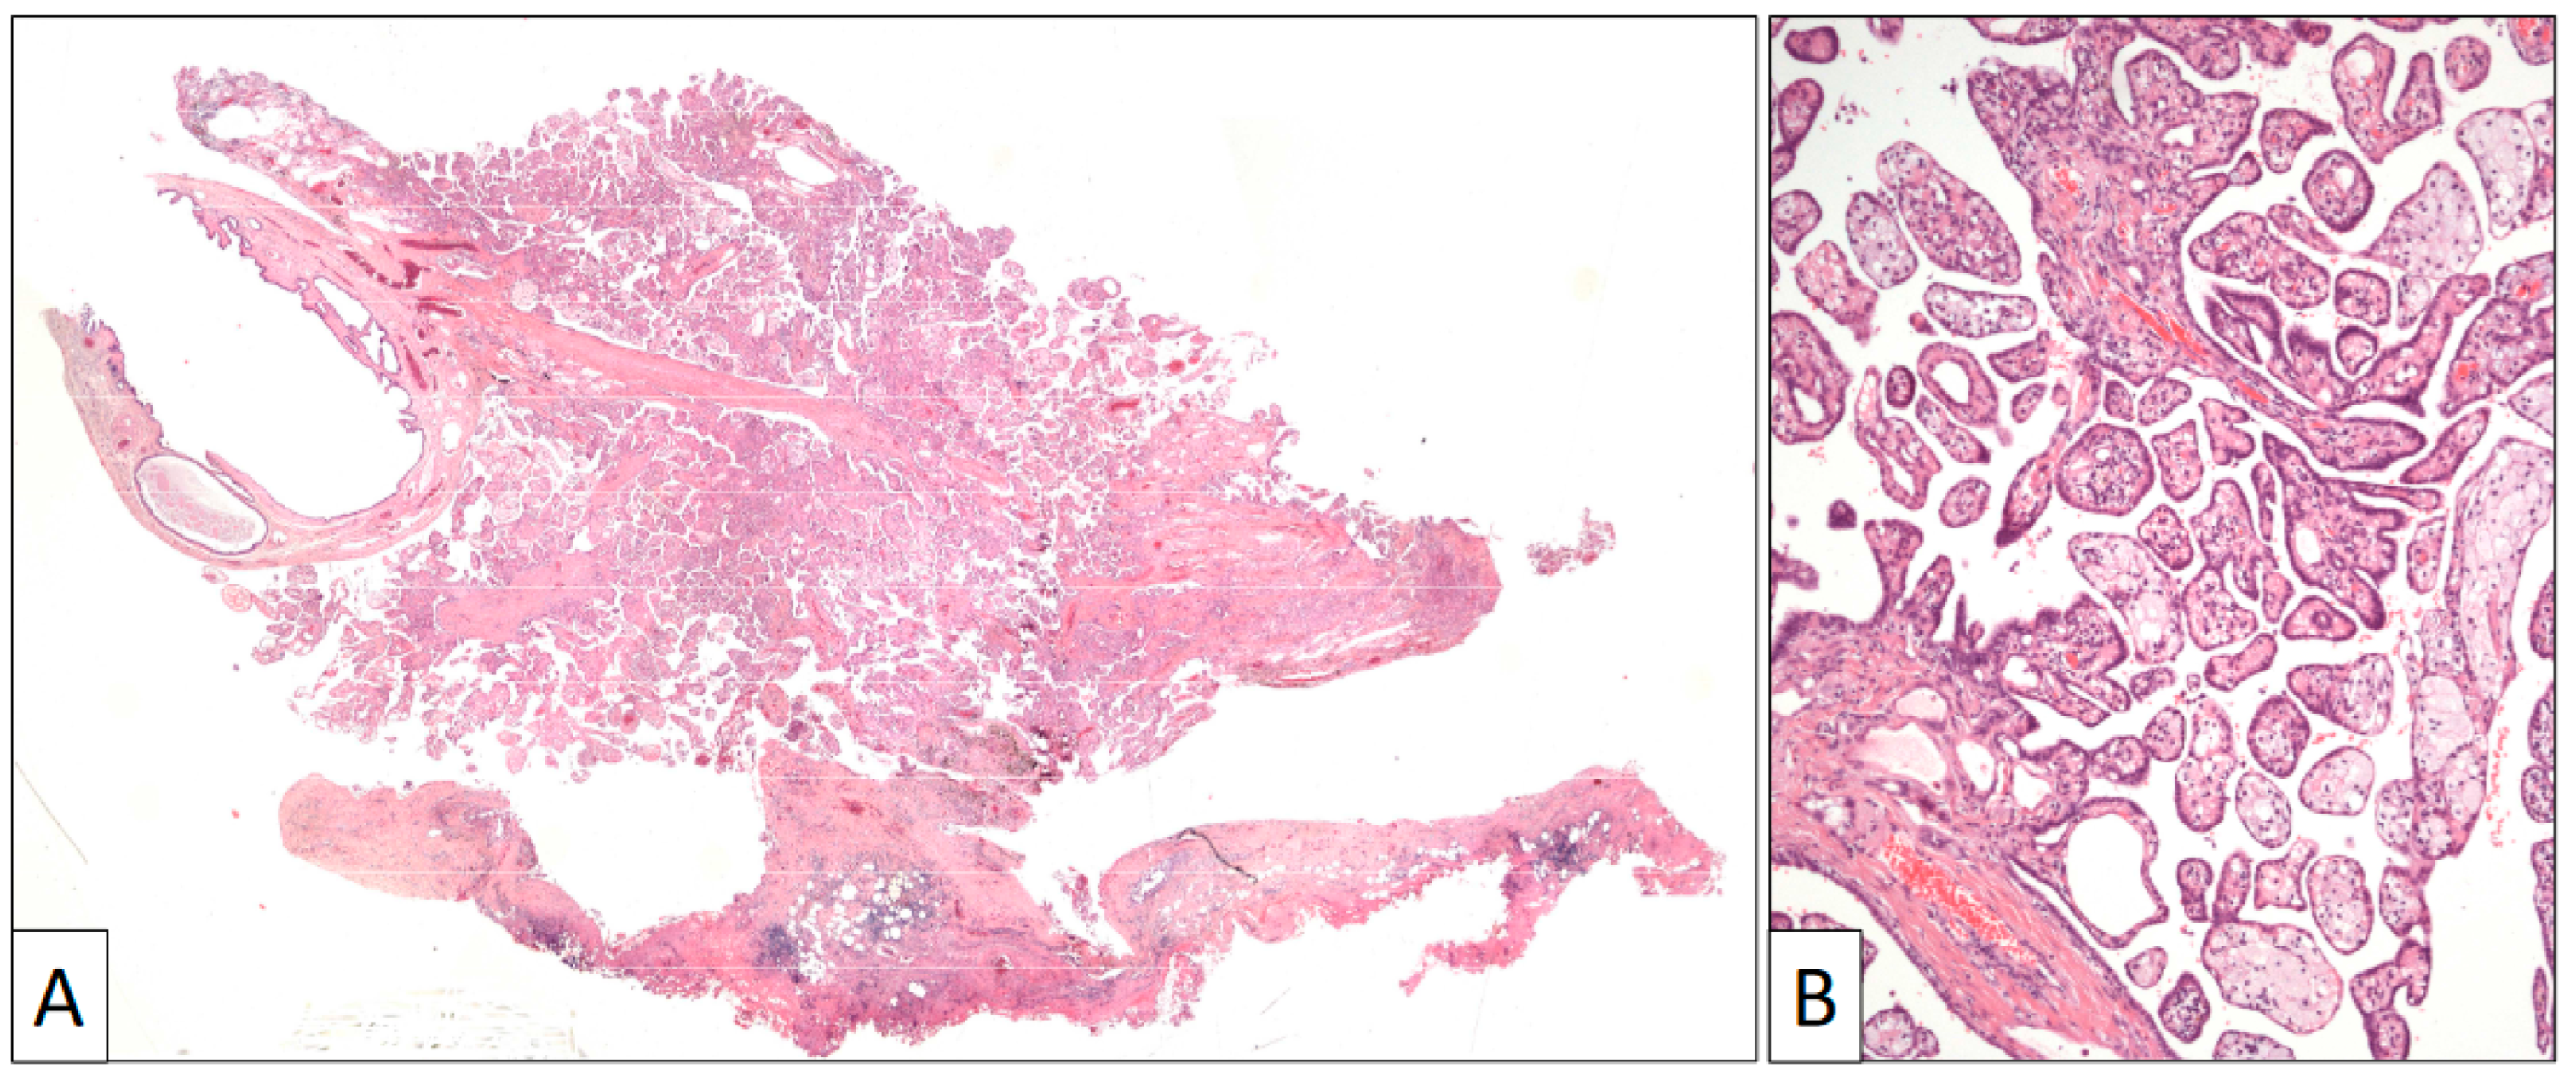

Figure 3.

(A) Panoramic view of a papillary benign mesothelioma showing an exophytic architecture and absence of infiltrative growth into the tunica vaginalis. (B) Papillary arrangement of the lesion (original magnification, ×100).

The surgical specimen consisted of an irregular fragment of tunica vaginalis that contained a villous exophytic lesion 1 cm in diameter (Figure 3). A preliminary diagnosis of a papillary mesothelial proliferation, undetermined for malignancy, was performed in the intra-operative study. A closer microscopic view to this lesion showed an intricated proliferation of papillary structures frequently filled with foamy cells and covered by a single row of flat to cuboidal cells with no atypia or mitoses. The tunica vaginalis to which this papillary lesion was attached consisted of a fibrous capsule with denudated surface and mild lymphocytic infiltration.

Immunohistochemistry (Figure 4) showed that calretinin, HMBE-1, and WT-1 were positive, demonstrating the mesothelial origin of the lesion. BAP-1 was strongly positive, as were cytokeratin and EMA. The proliferation index (Ki-67) was very low.

A diagnosis of well-differentiated papillary mesothelioma was made. The patient was alive and free of disease 2 years after the surgical resection.

Exophytic lesions like the second case in this study show an arborescent architecture. Papillae in these cases are covered by a single mesothelial cell layer. Foamy histiocytes fill in the stalks. An infiltrative pattern into the wall is usually lacking. These lesions appear in the literature as well-differentiated mesotheliomas [16,17,18,19,20,21].